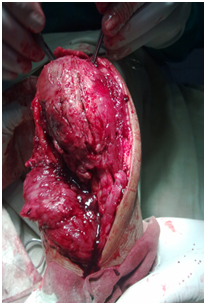

Under general anaesthesia tumour was exposed through posterior approach to elbow (Figure 3). Proximal ulna with tumour and 2cm of normal bone was excised (Figure 4). Another team of surgeons harvested required length of free fibular graft from upper fibula from ipsilateral leg. Head of the fibula was shaped to match the olecranon process of ulna and tensor fascia lata was covered over fibular head to act as articular surface (Figure 5). Graft was fixed to ulna using semi tubular plate and a K-wire was put for temporary immobilisation of elbow in 90degree flexion. Triceps tendon was sutured to the graft at proximal end. Specimen was sent for histopathological examination which confirmed the diagnosis of Osteoclastoma (Figure 6). Immediate post op X ray confirmed the proper fixation.

Figure 3 Per operative picture of tumour.